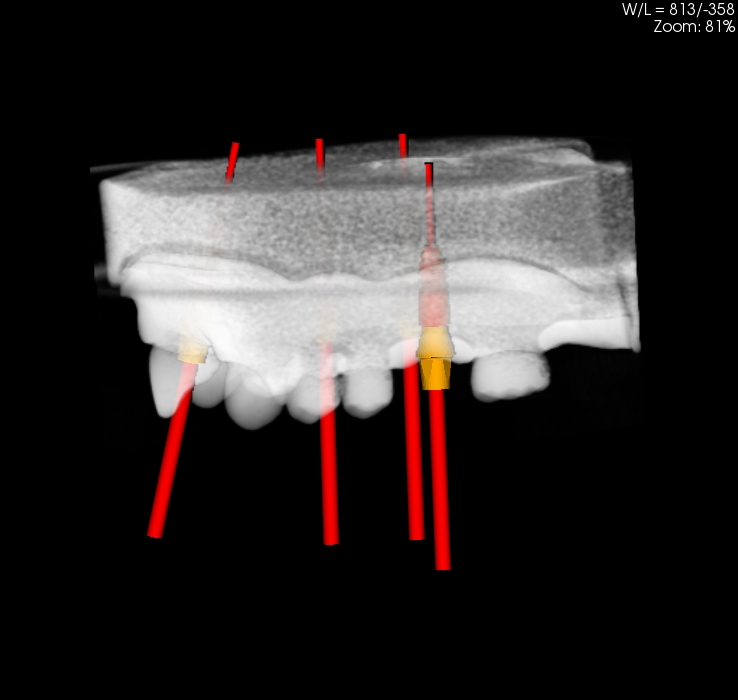

Oferujemy również szablony chirurgiczne przeznaczone do szkoleń z implantacji. Umożliwiają planowanie leczenia implantologicznego i przeprowadzenie szkoleń z wykorzystaniem plików CT, STL oraz druku 3D. Oferujemy nasze modele do szkoleń implantologicznych wraz z plikami DICOM i STL.

Pliki do wykonania szablonów można pobrać z naszej strony internetowej. Możemy je również dostarczyć wraz z modelami. Pliki te dostępne są dla modeli 10-1030, 10-3040, 10-3050, 10-5070,

Istnieje również możliwość dostarczenia szablomów w oparciu o pliki i informację o planowanej procedurze implantologicznej.

Model szczęki z zębami w pozycjach 11, 13, 14, 23, 24, 25 i 27, brakiem zębów w wygojonych pozycjach 21, 22, 26, 15, 16. Umieszczenie dwóch zagłębień imitujących niezagojone zębodoły w pozycjach 17 i 12 umożliwia ćwiczenie implantacji wczesnej i natychmiastowej. Wykonany jest z jednorodnego materiału o właściwościach zbliżonych do kości ludzkiej.  Model pokryty jest śluzówką, którą można nacinać i zszywać. Znakomicie nadający się także do  nauki implantacji odroczonej i planowania leczenia poekstrakcyjnego. Umożliwia również przedstawienie problemów związanych z prawidłowym umieszczeniem implantów pomiędzy koronami sąsiadujących zębów. Model można stosować w najbardziej popularnych na rynku fantomach jak i głowie fantomowej PROMEDICU 11-1000 jak również samodzielnie bez niego.